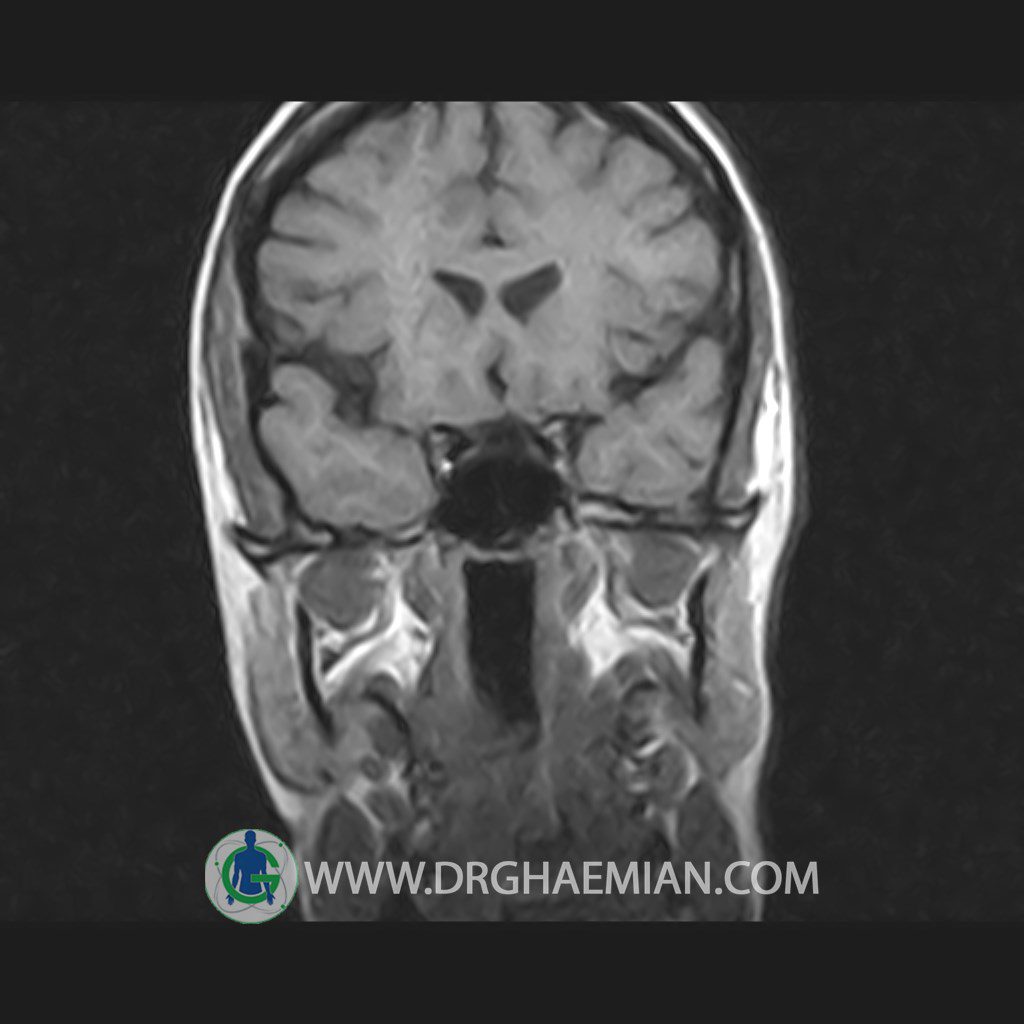

پزشکان اغلب از تصویربرداری ام آر آی برای تشخیص و درمان عارضه های پزشکی که فقط با استفاده از اشعه ایکس یا میدان مغناطیسی و امواج رادیویی قابل مشاهده است، استفاده می کنند. دستگاه ام آر آی تصاویر دقیق از ساختار های داخلی بدن ایجاد می کند. در این کیس هیپرپلازی هیپوفیز و آدنوم مشاهده می شود.

HYPOPHYSIS MRI

(with and without contrast)

Technique: Axial , coronal T1 , Axial , coronal , sagittal T2 , Axial, coronal T1 post Gd & 64 dynamic thin coronal slices.

The sella shows normal size , position and configuration .

The borders of its floor and walls are smooth and sharply defined .

The infundibulum is centered and of normal size .

The optic chiasm and suprasellar spaces appear normal .

The cavernous sinus and imaged portions of the internal carotid artery and carotid siphon are unremarkable .

Evaluable portions of the neurocranium show no abnormalities .

The sphenoid sinus is clear and pneumatized .

– Mild convexity at superior border of pituitary gland with post contrast homogeneous enhancement suggestive for pituitary hyperplasia & iso signal adenoma

is seen